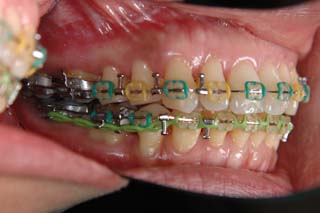

主訴:上の歯が出ている

診断名:顎関節症、下顎左右5欠損を伴う骨格性上顎前突

年齢:35歳

使用した主な装置名:TPB、マルチブラケット装置

抜歯/非抜歯および抜歯部位:非抜歯

治療期間:動的処置2年、経過観察3年

費用の目安:保険適応 自己負担金として30~50万

リスク、副作用:外科手術によるリスク、マルチブラケット治療に伴う歯根吸収など偶発症が発生するリスクがある。

強い骨格性の上顎前突が見られます。しばしば、口腔内所見では骨格のズレを歯の補償的な傾斜などでカムフラージュさせているため、あまり大したことのないズレにしか見えない事があります。また、上顎前突の場合は、下顎が関節の位置で知らず知らずのうちに前方へ大きく偏位させて噛んでいる事が多いです。このような場合は、咬合器に装着してみて初めて、治療方針が見えてくるかもしれません。どのような不正咬合であれ、大きなズレに対しては、外科的に骨のズレを改善する治療が理にかなっています。前後のズレ、垂直のズレと条件が重なってきた場合、より外科矯正での改善が望ましいでしょう。

一般的な外科矯正治療の流れは、術前矯正・外科矯正・術後矯正・保定治療と移行します。術後矯正では、手術後に僅かに見られる後戻りに対する処置や、刻々と変化する額関節の環境に対応して調節を続けます。特に大きな問題が無ければ6か月程度で保定治療に移行します。